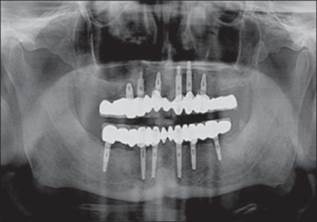

Un paciente de sexo masculino de 58 años había acudido al ala de pacientes externos de nuestro departamento, con una queja principal de falta de diente en los arcos maxilar y mandibular. El paciente quiere tener una prótesis fija ya que no estaba contento con la dentadura convencional [Figura 1] y [Figura 2] . Se registró un historial de casos adecuado para el paciente, incluido un historial médico que no era contributivo, con pruebas de laboratorio relevantes, exámenes dentales y orales. Se prepararon impresiones de diagnóstico y moldes. Se realizó un examen exhaustivo y el paciente estaba motivado para implantar prótesis. El mapeo óseo se realizó para evaluar el ancho del hueso, mediante el uso de ortopantamografía (OPG), se calculó la longitud del hueso disponible y se seleccionaron los implantes de tamaño apropiado [Figura 3]. Se preparó una plantilla quirúrgica para el maxilar y la mandíbula, y la posición de los implantes se decidió antes de la cirugía colocando un taladro en el implante.

Figura 3: Mapeo óseo y radiografía preoperatoria |